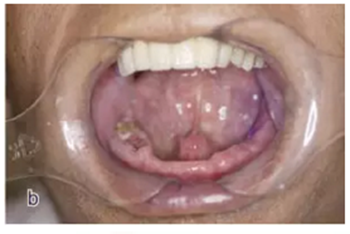

本案例為78歲男性患者,下頜義齒活動、固位差,口內(nèi)有殘根?;颊咭筮M行種植義齒修復(fù)。

術(shù)前拍攝錐形束CT,進行三維重建和種植方案規(guī)劃。從CT圖像中可以看出頜骨內(nèi)有骨島和殘根,為避免種植體植入骨島區(qū),考慮在兩側(cè)頦孔區(qū)種植4~5顆種植體,采用套筒冠進行即刻修復(fù)。從重建的結(jié)果中可知前牙區(qū)牙槽嵴呈刀刃狀。種植方案為:對前牙區(qū)牙槽嵴進行截骨修整,并在兩頦孔之間的區(qū)域內(nèi)植入5顆種植體。